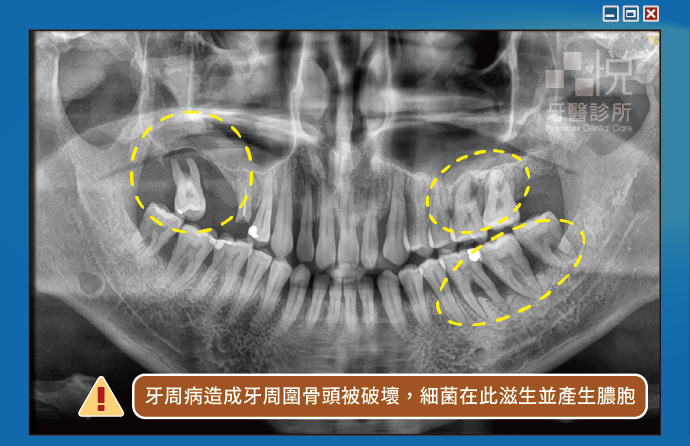

當牙齦或牙周嚴重發炎感染時,會在牙周旁邊的牙齦產生膿包。且當身體免疫力不佳時還會反覆產生膿包。